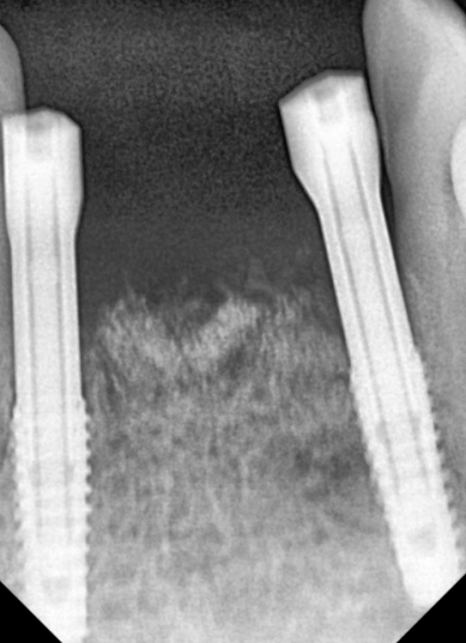

이 환자분은 과거에 아래

중앙 앞니(#31, 41)가 흔들리기 시작했을 때,

발치가 두려워 철사로

양옆 치아까지 넓게 묶어두셨다고 해요~

251022

당장 흔들림이 없으니

안심하고 오랜 시간을 보내셨지만,

정작 뿌리 끝에 박힌 염증 원인은

그대로 남아 있었죠.

결국 중앙 앞니에서 시작된 염증은

조용히 옆 치아(#32, 42)까지 퍼져나갔습니다.

내원 당시에는

이미 철사로도 감당할 수 없을 만큼

4개의 치아가 한꺼번에

심하게 흔들리고 있었고,

251028

주변 잇몸뼈가 광범위하게 녹아내려

결국, 앞니 4개를 모두 발치하고

임플란트를 진행했습니다.